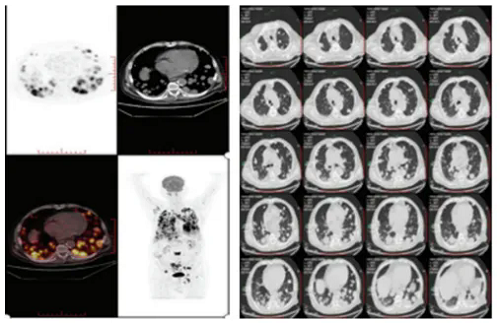

图2 从左图可以看到,经过治疗后患者全身肿瘤有非常明显的减少

经过一段时间的治疗后,患者的病情出现了显著改善。最明显的变化是,其原发肝部肿瘤体积缩小了60%,而肺部、淋巴结及骨骼中的转移病灶则减少了高达90%。